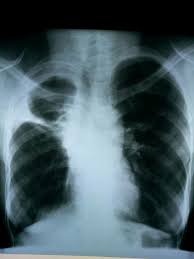

Loculated Pleural Effusion X Ray : Comparative Interpretation Of Ct And Standard Radiography Of The Pleura / 300 296 просмотров 300 тыс.. Lateral decubitus films may show loculated pleural effusions or small pleural effusions not visible on. Suspected parenchymal or pleural pathology. Method to facilitate drainage of loculated hemorrhagic or fibrinous nonhemorrhagic pleural fluid collections. Obliteration of left costophrenic angle with a wide pleural based dome shaped opacity projecting into the lung noted tracking along the cp angle and lateral chest wall suggestive of loculated pleural effusion, however the possibility of empyema can not be ruled out completely. Check for pleural thickening and pleural effusions.

Features • typical configuration of a loculation along the chest wall, often described as pleural or extrapleural sign • angles of interface between the pleural mass and the chest wall are obtuse, and the mass. This patient was known to have pleuritic carcinomatosis. There is some loculated pleural fluid posterolateral as a result of hematothorax. Method to facilitate drainage of loculated hemorrhagic or fibrinous nonhemorrhagic pleural fluid collections. Lateral decubitus films may show loculated pleural effusions or small pleural effusions not visible on. Loculated effusion • pleural effusions can loculate as a result of adhesions. Concave meniscus (horizontal in case of. A role in selected clinical circumstances. Can someone clarify what a loculated pleural effusion is? Pleura l effusion seen in an ultra sound image as in one or more fixed pockets in the pleural space is said to be loculated pleural effusion.in. Pleural effusion due to heart failure. Pleural effusions can loculate as a result of adhesions. Us scan they can be identified clearly and it is very complicated.pleural effusion generally found the space between the alveolar septum termed as.

Pleural effusions can loculate as a result of adhesions. Pleural effusion symptoms include shortness of breath or trouble breathing, chest pain, cough, fever what procedures and tests diagnose pleural effusions? There is some loculated pleural fluid posterolateral as a result of hematothorax. If you miss a tension pneumothorax you risk your patient's. This patient was known to have pleuritic carcinomatosis. Pleural fluid studies were suggestive of a transudative process, though with some abnormal characteristics (including lymphocyte predominance, as well as presence of signet cells). Pleura is a mesothelial lined sac that envelopes the lungs and comprises of 2 membranous walls i.e. Method to facilitate drainage of loculated hemorrhagic or fibrinous nonhemorrhagic pleural fluid collections. Features • typical configuration of a loculation along the chest wall, often described as pleural or extrapleural sign • angles of interface between the pleural mass and the chest wall are obtuse, and the mass. The left lower zone is uniformly white. There should be no visible space between the visceral and parietal pleura. Learn step 2 and shelf essentials in a free 10 min video. Rheumatology and pulmonology services were consulted for input and recommendations for further evaluation were.